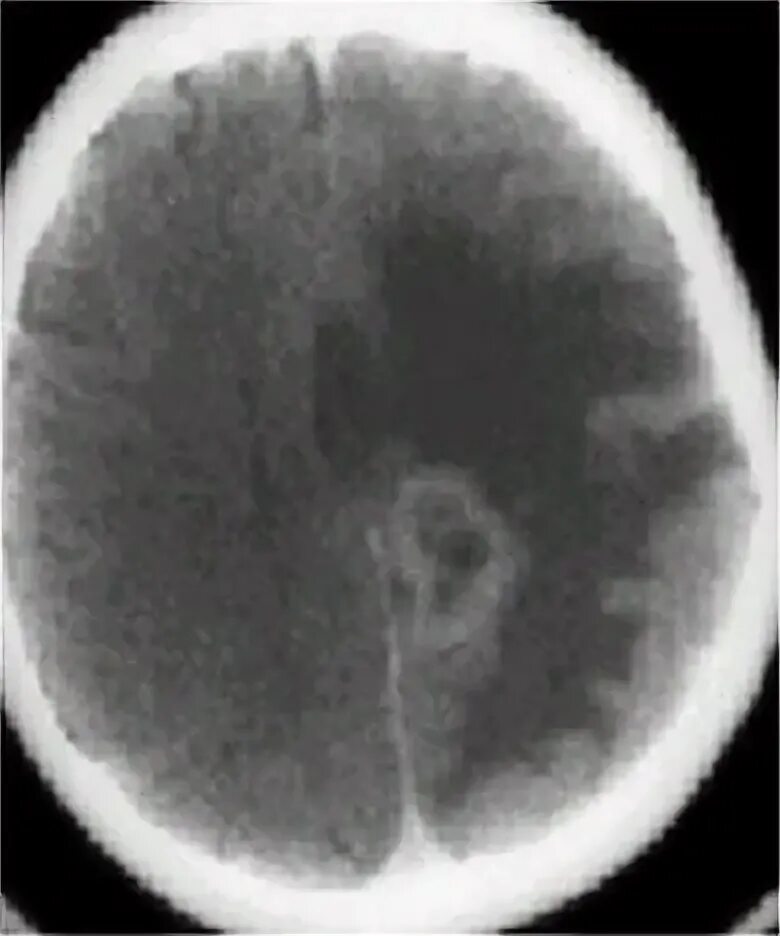

Метастазы головного мозга кт